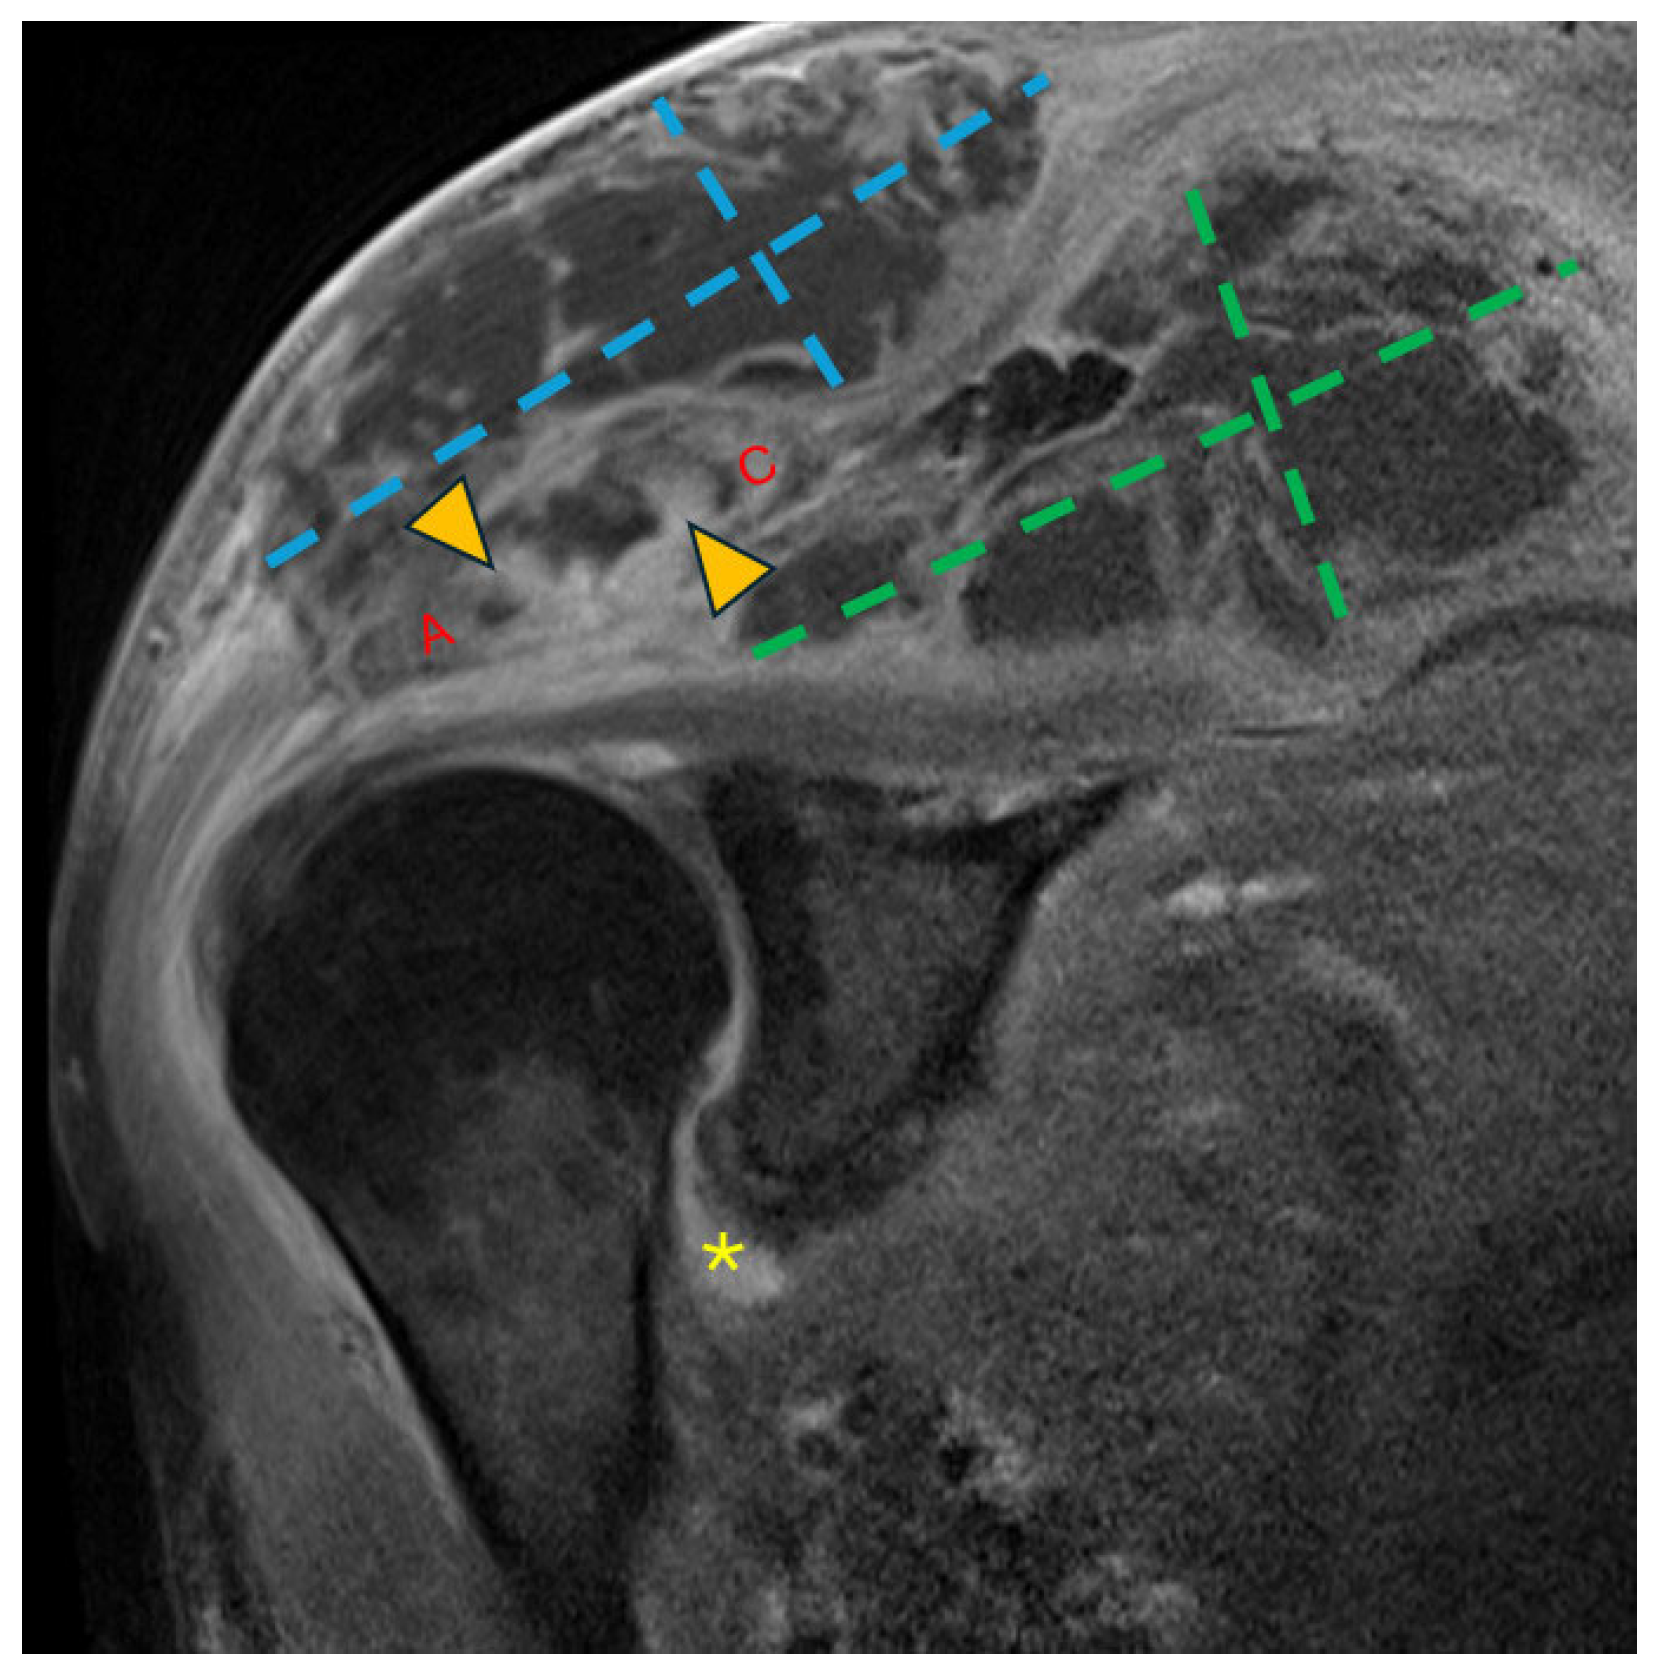

Figure 2.

Coronal T1 fat-saturated magnetic resonance image (MRI) post-contrast (gadolinium) at the level of the AC joint (red A = acromion; red C = clavicle). Multilocular peripherally enhancing collections are present in the superficial subcutaneous tissue directly above the AC joint (blue dashed lines) and in the supraspinatus fossa (green dashed lines). Marrow enhancement (yellow arrowheads) of the acromion and clavicle across the AC joint is consistent with osteomyelitis. Synovitis in the axillary recess of the glenohumeral joint (yellow asterisk) raised concern for glenohumeral septic arthritis.